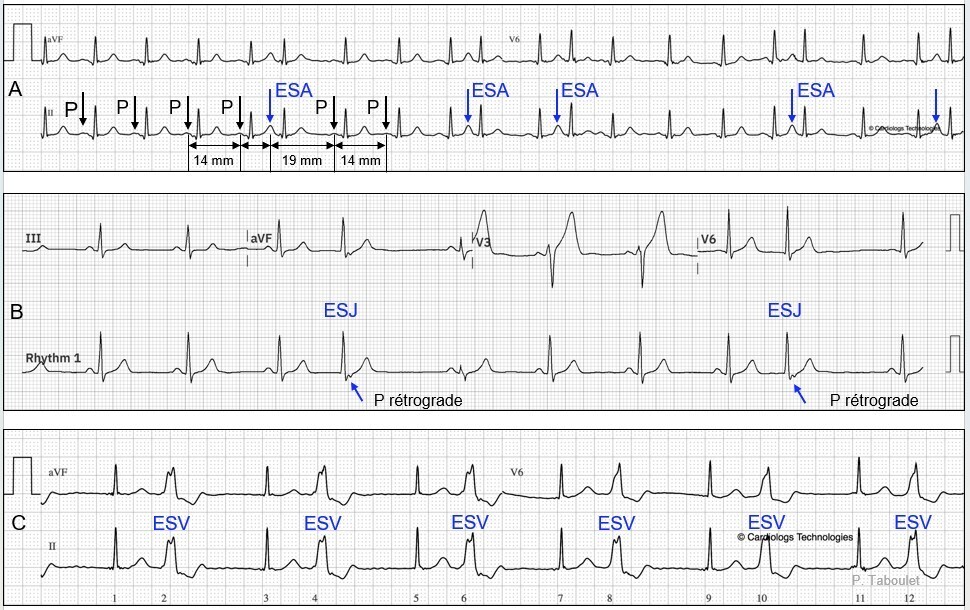

• les extrasystoles atriales, jonctionnelles et ventriculaires (figure 2),